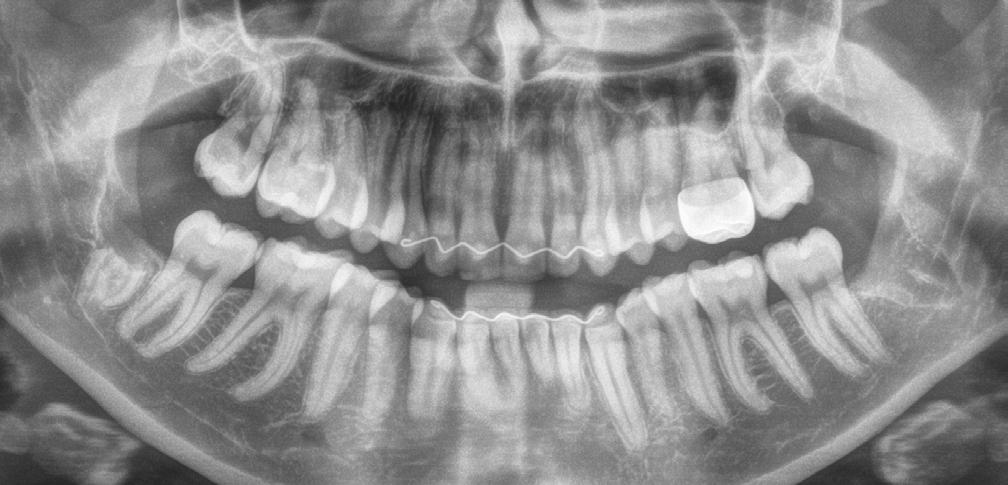

An orthopantomogram (OPG) revealed RL8 and LL8 were mesioangularly impacted and their roots were crossing both upper and lower white lines of the inferior alveolar canal (IAC). LL8 roots showed darkening of root at the level of IAC (Fig 1).

It was decided to request a Cone Beam CT to substantiate findings of the routine OPG in relation to the IAN.

CBCT revealed the following findings:

LL8: IAC was running buccal to roots of LL8 which had 3 roots (Fig 2).

RL8: IAC was seen running between the buccal root which was hooked mesially and lingual roots at its apex, vulnerable to surgical injury (Fig 3).